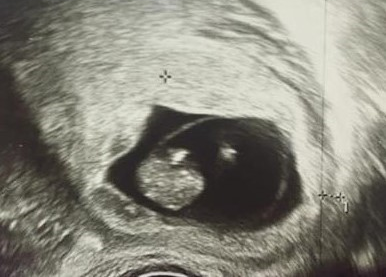

Для уточнения ситуации было проведено повторное УЗИ органов малого таза в динамике. Данные УЗИ от 20.07.2020: тело матки анатомически правильное, гематома на 15 мм выше плодного яйца. Толщина миометрия в зоне рубца 3 мм. Миоматозные узлы отсутствуют. В полости матки в области нижнего сегмента расположено одно плодное яйцо, 19 мм в диаметре (7–8 недель). В полости матки эмбрион: КТР 19 мм (соответствует восьми неделям беременности), хорион в области послеоперационного рубца. Сердцебиение эмбриона ритмичное, 173 удара в минуту. Шейка матки – внутренний зев сомкнут. Правый яичник не изменен, левый яичник содержит желтое тело диаметром 16 мм. Маточные трубы не визуализируются, свободной жидкости в сводах нет. Заключение: беременность 8–9 недель. Имплантация плодного яйца в области рубца на матке (рис. 1, 2).

Рис. 2. Ультразвуковое исследование органов малого таза. Беременность в рубце на матке после кесарева сечения. Истончение миометрия в зоне рубца до 3 мм. Дата проведения: 20.07.2020

УЗИ является одним из главных методов диагностики беременности, в том числе и эктопической. Диагноз эктопической беременности в рубце после кесарева сечения был поставлен на основании описанных в литературе критериев: визуализация гестационного мешка на уровне рубца после выполненного ранее кесарева сечения, в нижнепереднем отделе миометрия, истончение миометрия в этой зоне до 3 мм. Наличие ретрохориальной гематомы и незначительного кровотечения из влагалища указывало на начинающееся прерывание беременности в рубце на матке.